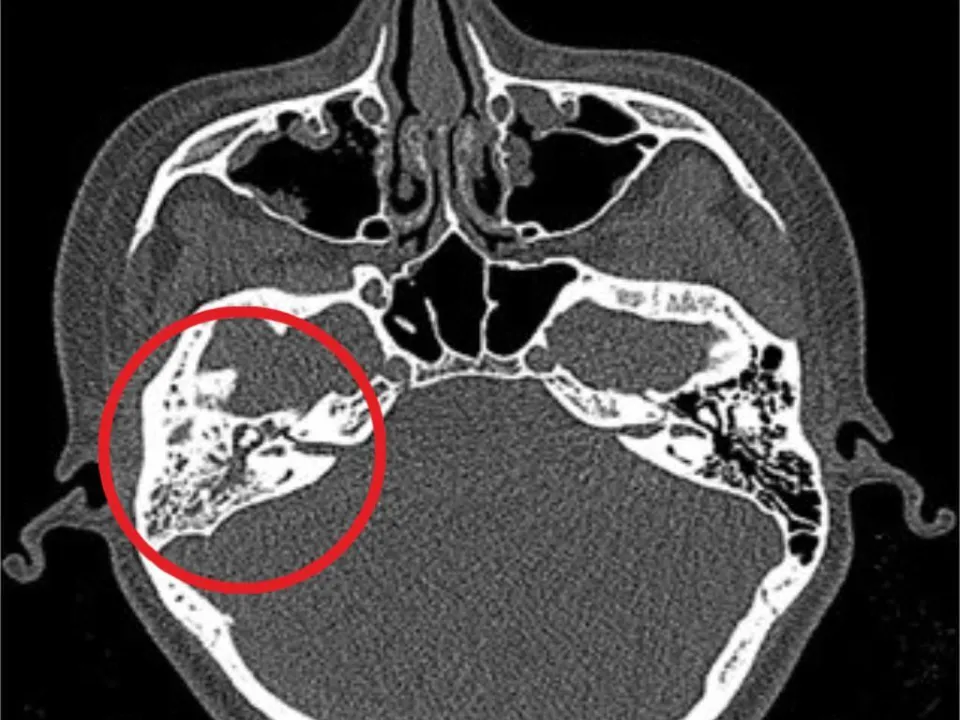

После осмотра оториноларингологи провели компьютерную томографию височных костей, которая подтвердила диагноз: острый правосторонний гнойный отит, острый правосторонний мастоидит и нейропатия лицевого нерва справа.